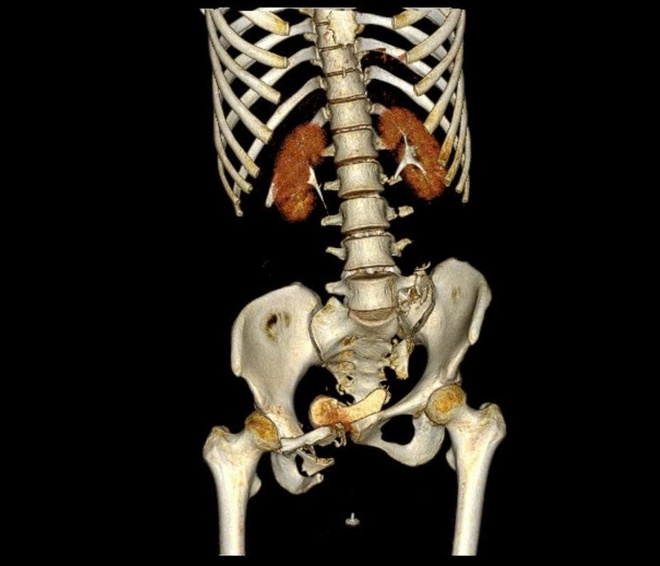

Bệnh nhân này là chị N.T.H (24 tuổi, ngụ TP HCM). Trước đó, tối 13-9, chị H. bị xe container tông, được chuyển đến Bệnh viện Quân y 175 trong tình trạng sốc đa chấn thương nặng: dập phổi phải; vỡ bàng quang và buồng trứng phải, gây xuất huyết ổ bụng; gãy gai ngang đốt sống L2–L5; gãy phức tạp khung chậu kiểu "gió thổi".

Các bác sĩ đánh giá, hội chẩn tình hình của bệnh nhân (trái) cùng hình ảnh chụp Xquang xương chậu của bệnh nhân (phải)

BSCKI Trần Quang Khanh, Khoa Phẫu thuật chi dưới, Viện Chấn thương Chỉnh hình, Bệnh viện Quân y 175, một trong những bác sĩ trực tiếp tham gia phẫu thuật, cho biết chị H. bị gãy khung chậu kiểu "gió thổi" - một dạng gãy rất phức tạp, chiếm khoảng 6% các trường hợp gãy khung chậu. Đây là loại gãy do chấn thương năng lượng cao, kết hợp giữa lực nén trước–sau và lực tác động bên, khiến một bên cánh chậu mở ra, bên còn lại khép lại, tạo hình ảnh đặc trưng như 'bị gió thổi'.

Thường tổn thương còn đi kèm gãy xương cùng và tổn thương khớp mu, làm mất vững toàn bộ vòng chậu, gây nguy hiểm tính mạng nếu không được xử trí đúng cách.